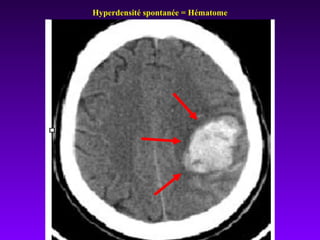

En urgence reconnaît la lésion hémorragique

sous forme d’une zone spontanément

hyperdense.

La lésion ischémique est sans traduction

(en phase initiale) ou se manifeste par une

zone hypodense (après 24 h).

TDM cérébrale

Hyperdensité spontanée = Hématome